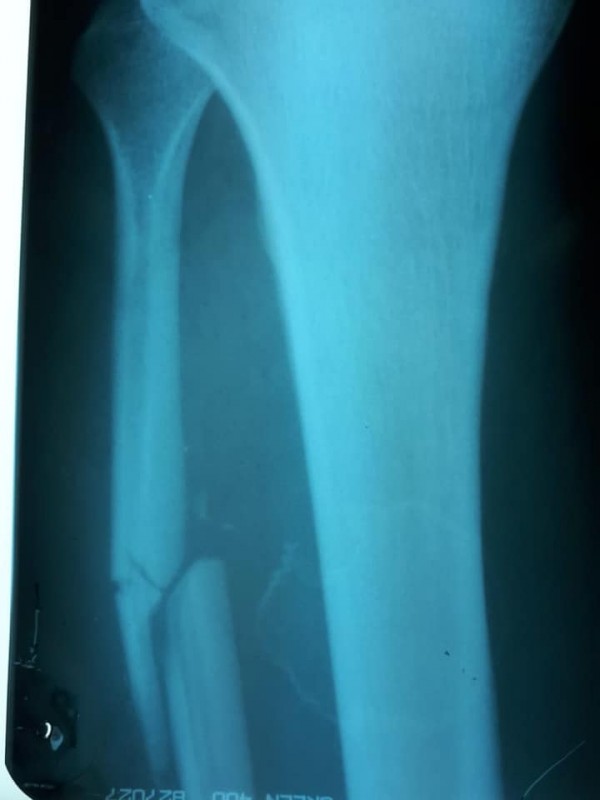

"Честно говоря, я лично думал, что ему просто "отсушили" бедро лоу-киками и гематома скоро спадет. Сегодня на рентгене, по возвращении на родину, выяснилось, что Алиби во втором бою сломал малую берцовую кость! Как можно с такой травмой даже просто ходить, а не биться и завоевать медаль на чемпионате мира - для меня загадка, удивление и восхищение!" - поделился Махметов.

По словам Махметова, у Алиби осколочный перелом со смещением берцовой кости. Спортсмену понадобится операция.